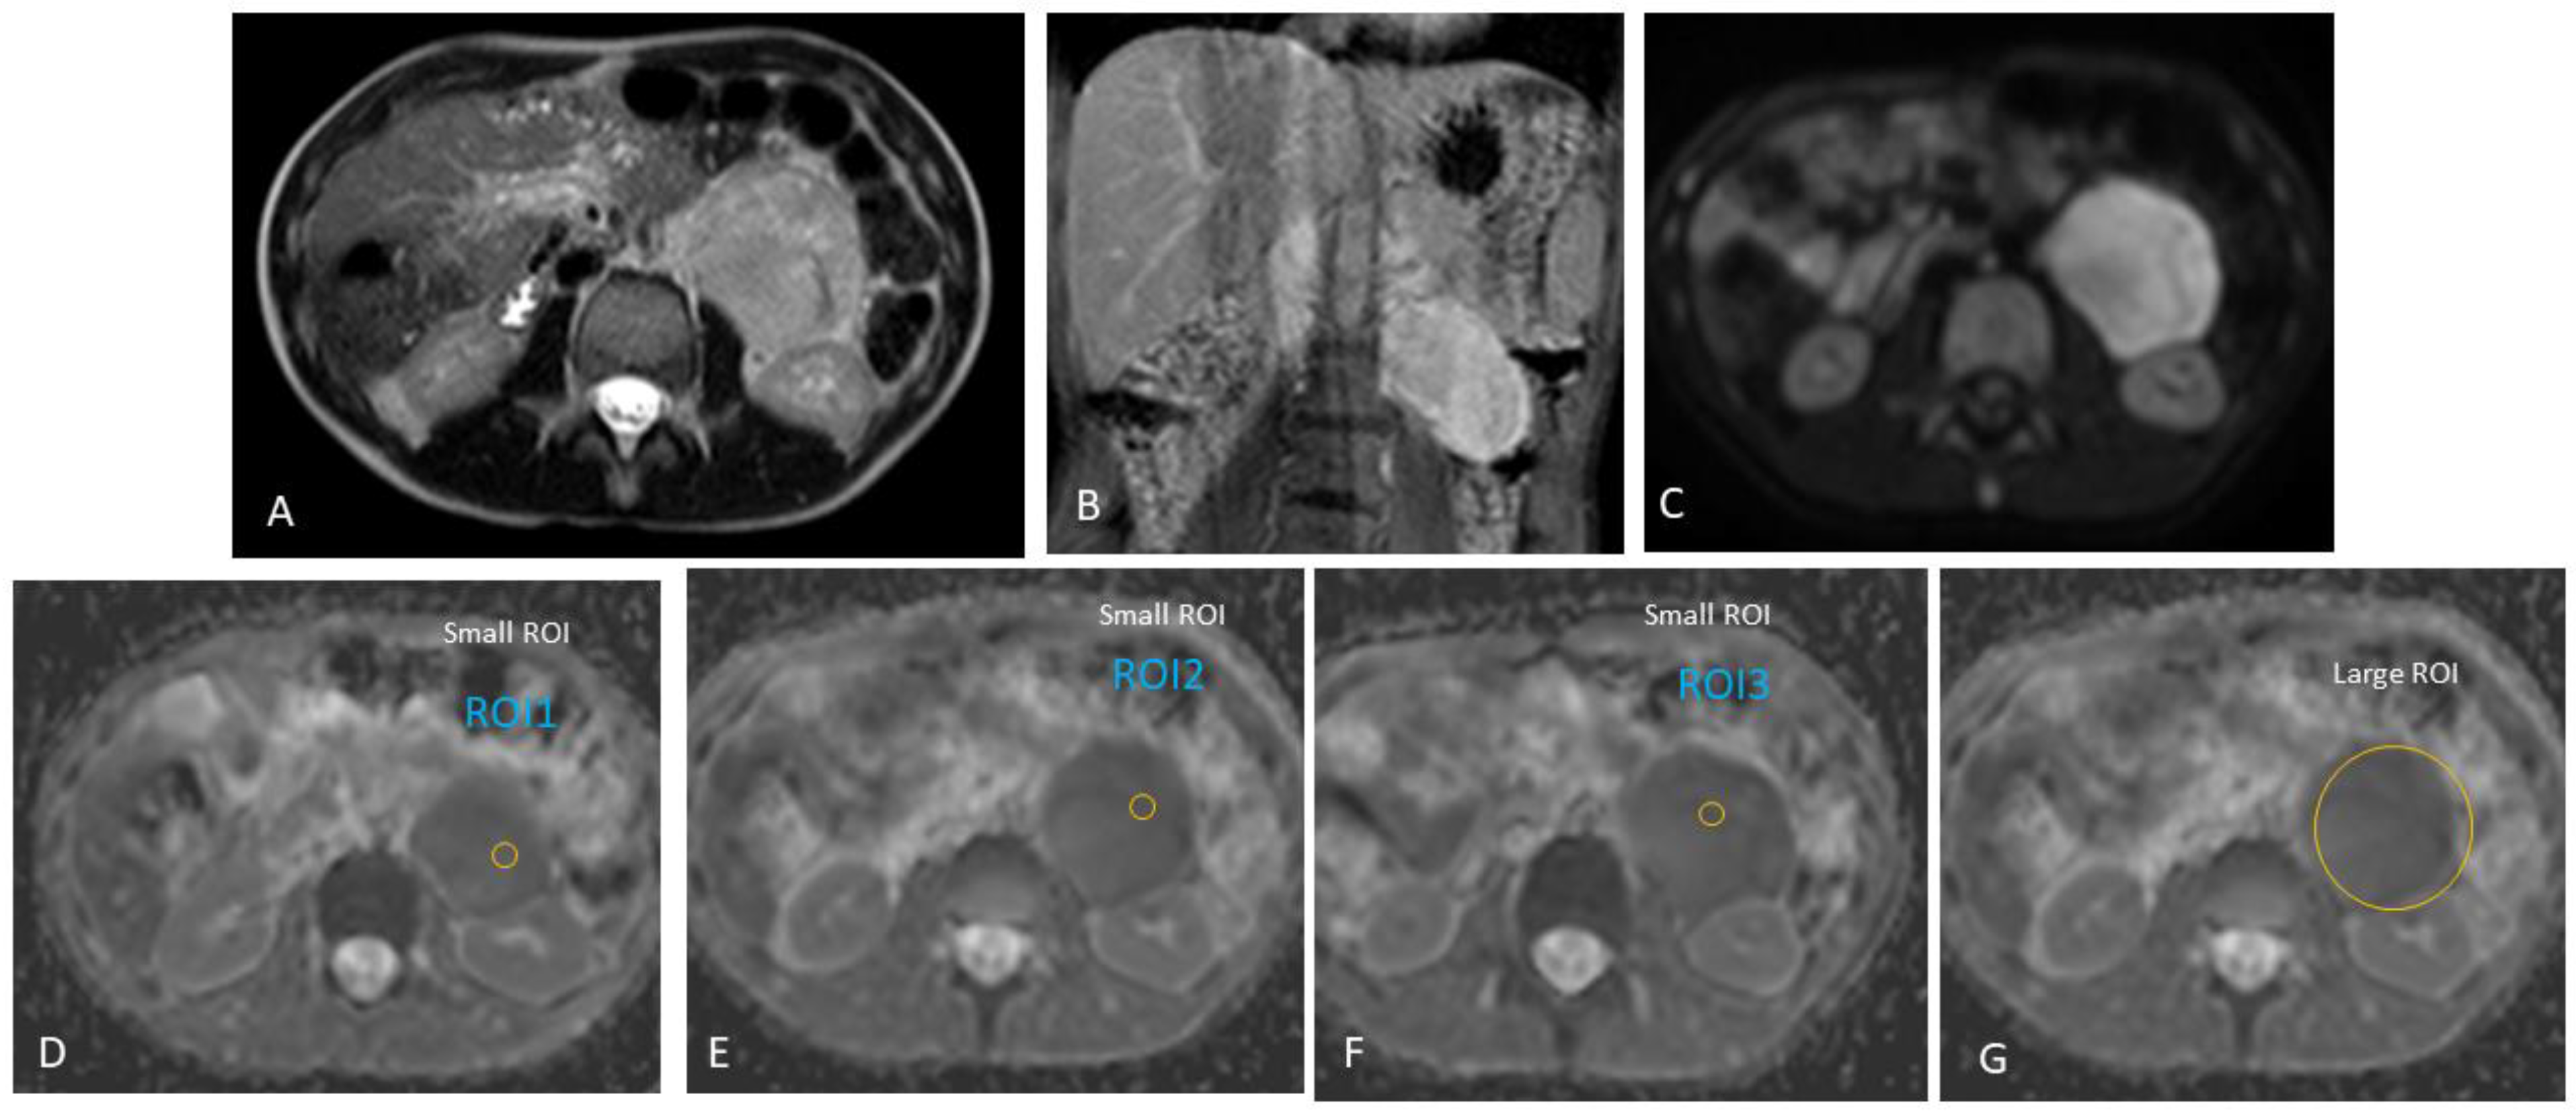

2.3.2. MRI Interpretation